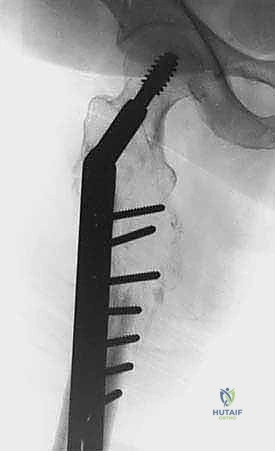

3. جراحات تخفيف الضغط عن العمود الفقري (Spinal Decompression & Stabilization)

عندما يضغط الورم على الحبل الشوكي، يقوم الفريق الجراحي بإزالة الجزء العظمي الضاغط (Laminectomy) وتثبيت الفقرات باستخدام براغي ودعامات معدنية. يمكن أيضاً حقن أسمنت عظمي طبي (Kyphoplasty) لتقوية الفقرة الهشة وتخفيف الألم فوراً.

| العمود الفقري (الفقرات) | انضغاط الحبل الشوكي، الشلل. | تخفيف الضغط العصبي + تثبيت الفقرات بمسامير + حقن أسمنت طبي. |